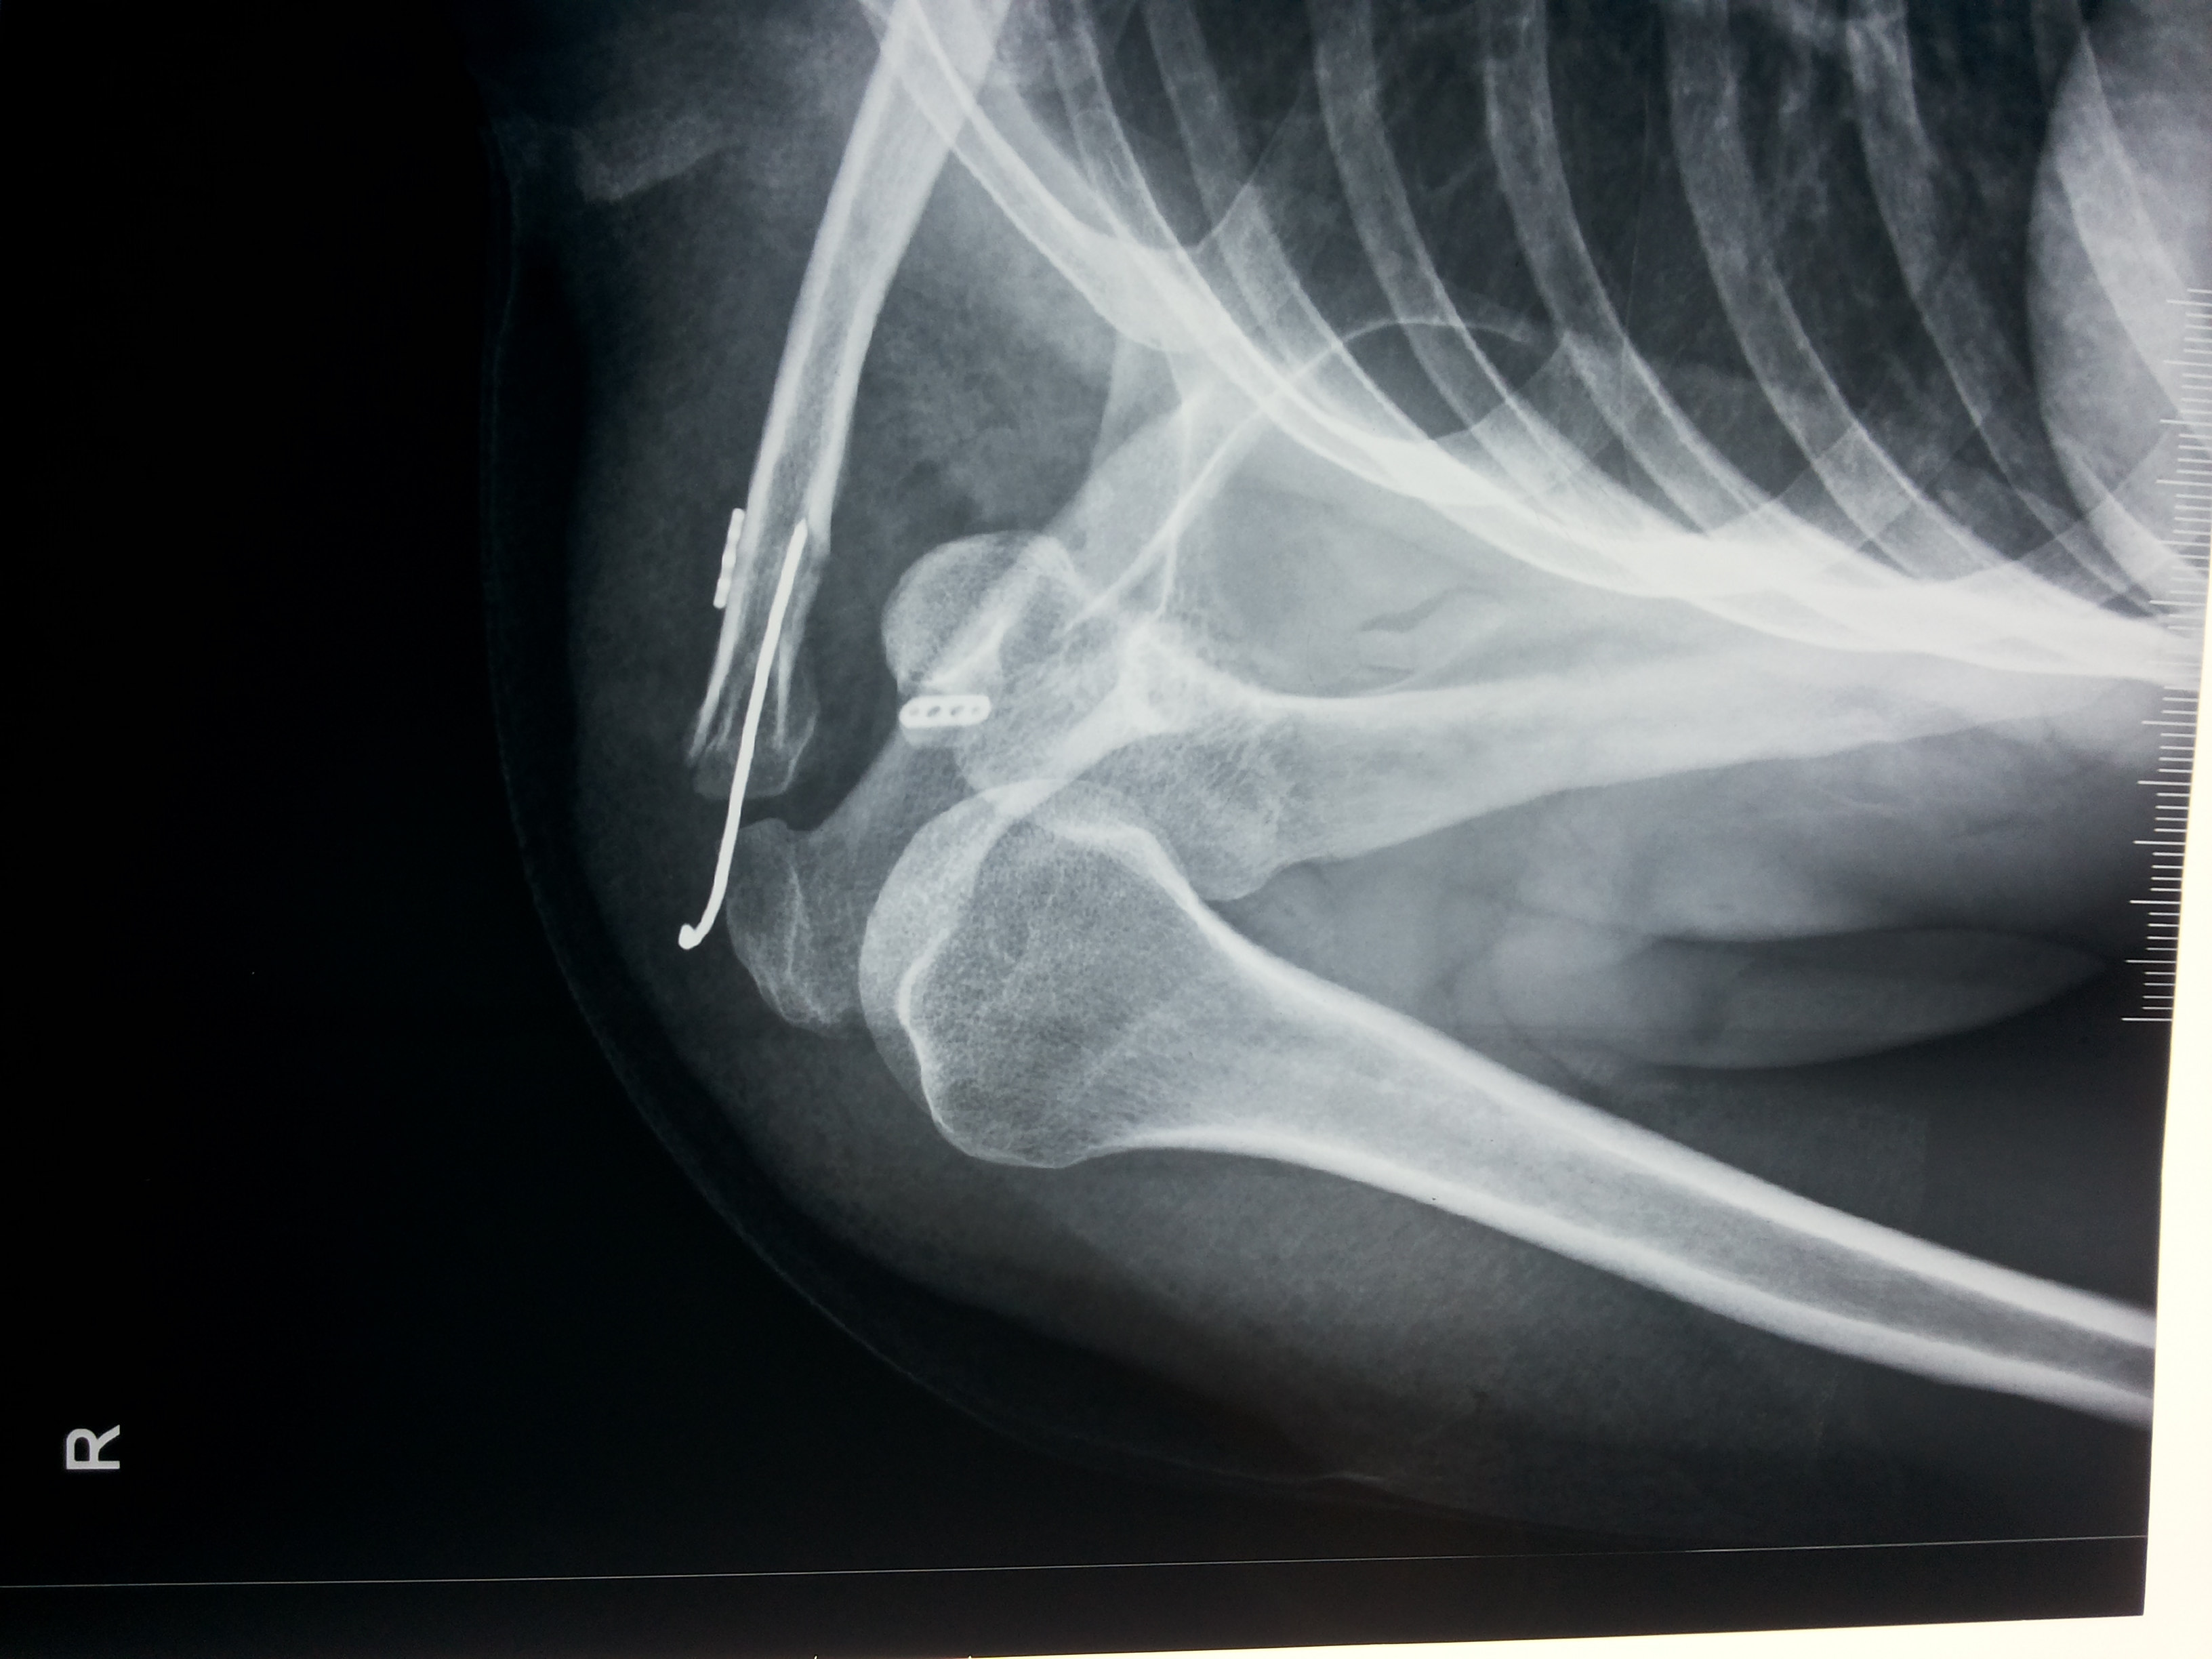

In order to determine the cause of a fracture, a doctor will inquire about the circumstances involved. A physical examination will then be performed to determine the cause. They will often order an X-ray and, in some cases, an MRI or CT scan in order to fully assess the fracture.